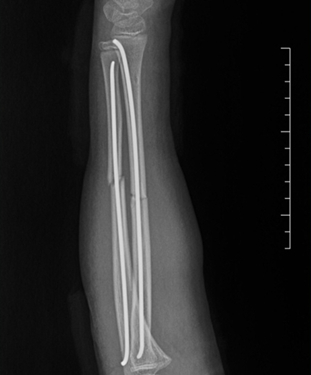

完善术前准备后,在麻醉科的配合下,周欣、冯晓军副主任医师为患儿实施了左尺桡骨骨折闭合复位弹性髓内钉内固定术。利用手臂上2个仅1cm的小切口就顺利完成了手术。术后,患儿复查X线,效果良好,患者家属对此感到满意,感谢连连。

据周欣副主任医师介绍:儿童常见的骨折有股骨干骨折、胫骨骨折、尺桡骨双骨折等,针对这类长管状骨骨折,可使用弹性髓内钉这一微创技术,对儿童的骨骼发育影响小。由于儿童骨折愈合较快,4-6个月即可取出内固定。

弹性髓内钉技术被国外专家称为“上帝送给儿童的礼物”,该技术可以在保护骺板不受损的前提下,利用三点固定原理,微创治疗儿童四肢骨折,实现了患儿家长痛苦少、疤痕小的愿望。目前我院已常规开展此类手术。(图文/浦梦安 编辑/孙炜 审核/杨居艳) |